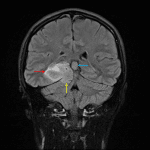

- Lobular T1 hypointense, T2 hyperintense mass centered in the medial right temporal lobe (with involvement of the hippocampus and parahippocampal gyrus) measuring 4.5 x 4.3 x 3 cm

- The mass bulges inferiorly through the tentorial notch and contacts the superior margin of the cerebellum

- Incomplete internal signal suppression on FLAIR

- No corresponding restricted diffusion or enhancement

- No surrounding parenchymal edema

- Associated local mass effect without evidence for hydrocephalus

IDH-mutant astrocytoma